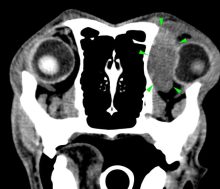

What’s your diagnosis? Computed Tomography Case 3

Diagnostic Imaging |

A 7-years-old Labrador was presented to with lethargy, anorexia and exophthalmos. A CT scan of the head revealed the ...